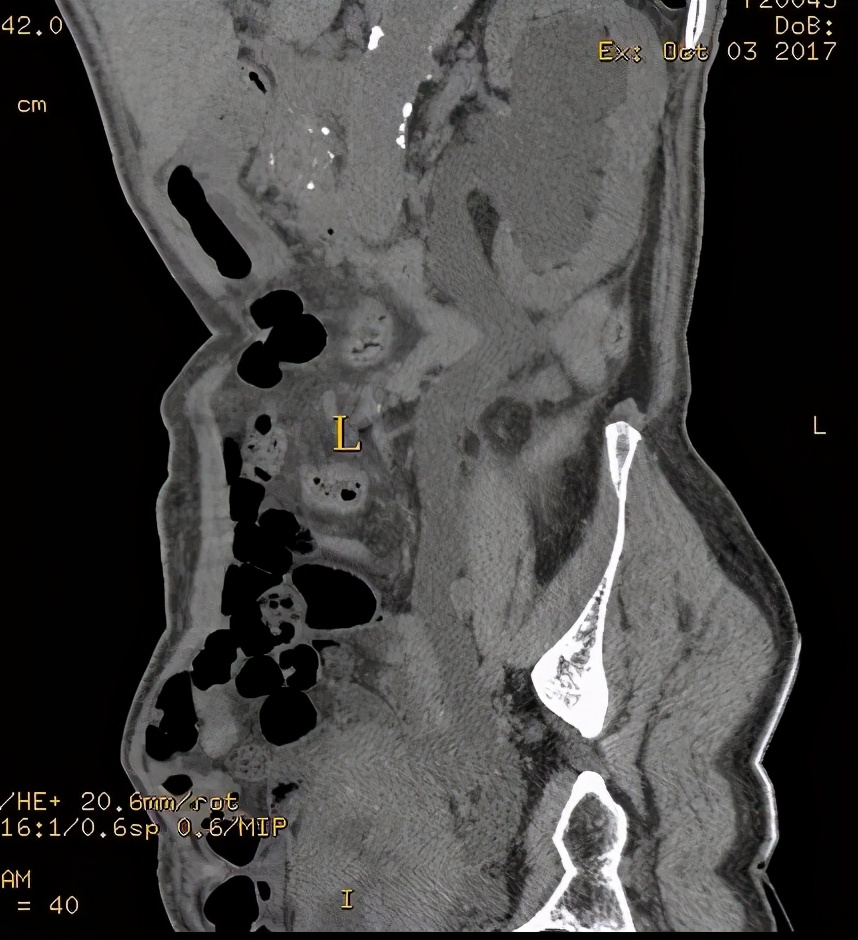

上图所示:38岁男患,血尿待查。CT尿路造影检查示膀胱左后壁增厚,有强化表现,阻塞左侧输尿管膀胱入口处,致左肾积水、左侧输尿管扩张。考虑膀胱癌可能。